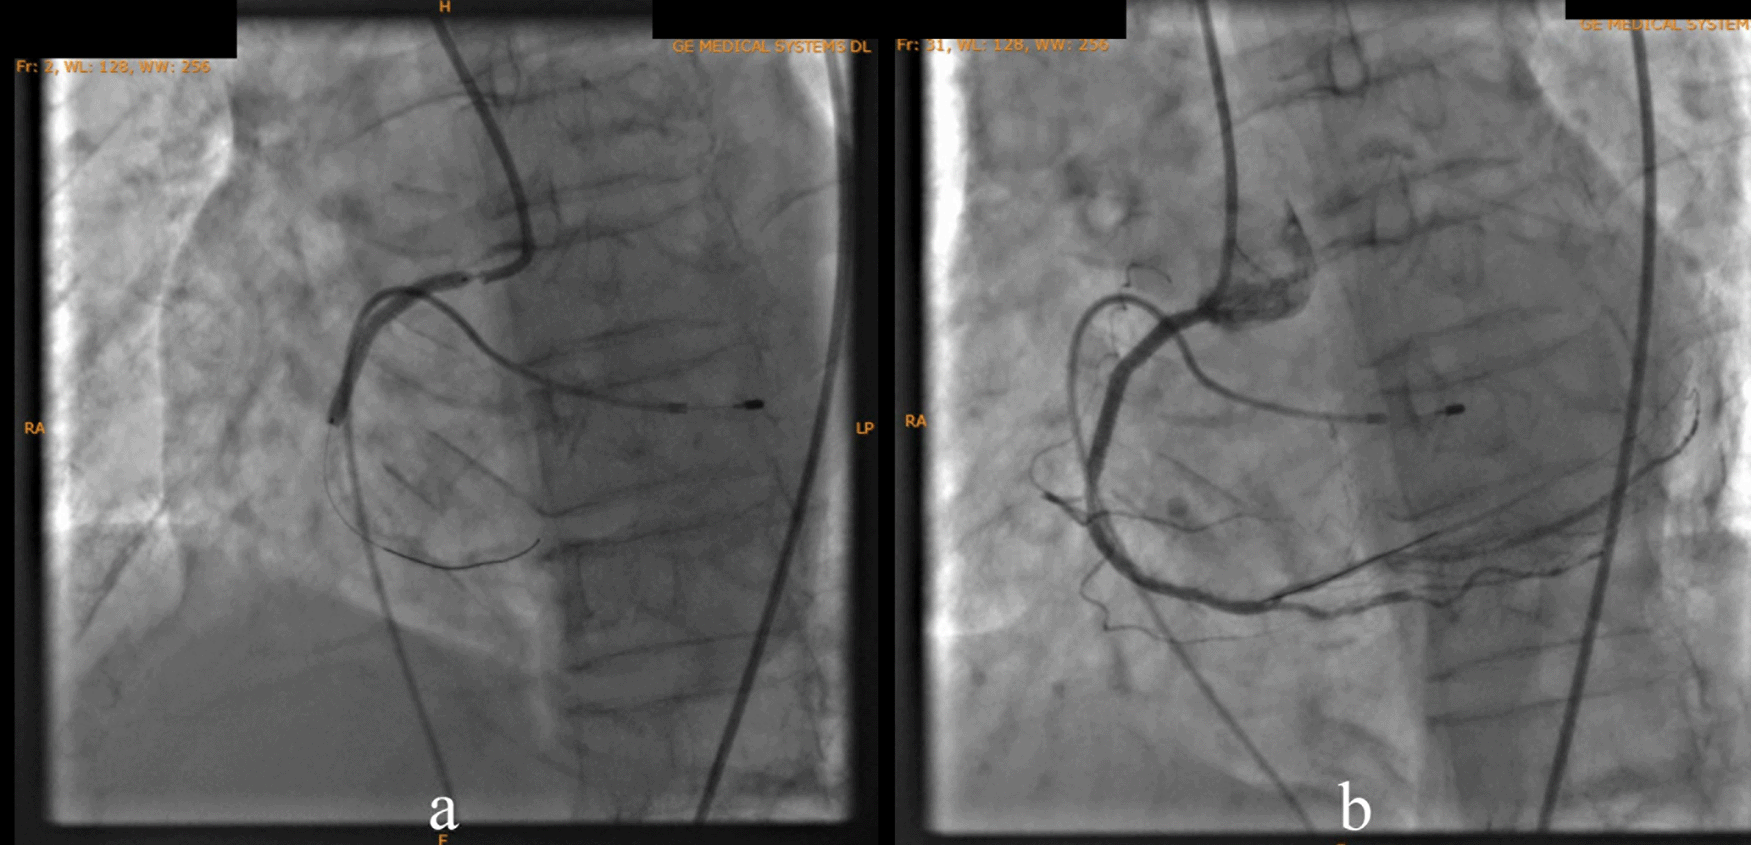

According to the DCA, the total occlusion was at the proximal right coronary artery (RCA) (Figure 2). There was insignificant stenosis in the proximal-mid left anterior descending artery. Besides, there were no stenosis on the left circumflex artery and the left main coronary artery. Primary PCI at the RCA was conducted using drug eluting stent (DES) promus and then thrombolysis in myocardial infarction (TIMI) grade 3 flow was shown at the RCA (Figure 3). Electrocardiography was also conducted after the installation of the pacemaker (Figure 4).